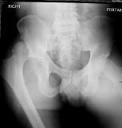

When younger patients sustain a hip dislocation, there has usually not been a previous hip replacement, and it is usually a posterior hip dislocation (out the back) caused by significant force, that results in a fracture of the hip socket (acetabulum). The fractured socket then prevents the hip bone (femoral head) from staying within the hip joint once it is put back. X-rays show the direction of the dislocation and if there is an associated fracture of the hip bone (femur) or socket (acetabulum). A physical examination is important to check for injuries to other structures, such as muscles or nerves.

When older patients sustain a hip dislocation, there usually has been a previous hip replacement on the affected side. These dislocations can be in any direction and may be caused by trauma, such as a fall, or normal daily activities, such as getting out of a chair or car. Dislocations caused by normal activities or when the hip has dislocated numerous times usually indicate that the hip replacement components are not in the proper position. X-rays show the direction of the dislocation, the approximate position of the hip replacement components, and whether there has been a fracture of the hip bone (femur) or socket (pelvis). When an X-ray does not provide all of the information required, a CT scan may be necessary to find out the exact position of the hip replacement components and to better image any fractures that may be present